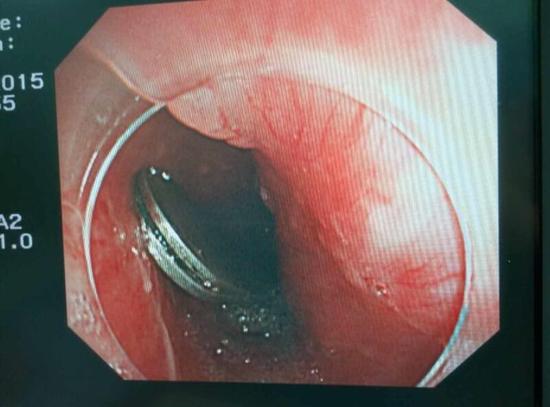

醫(yī)生從華先生胃里取出的鑷子和打火機

手術(shù)中,范醫(yī)生通過胃鏡準(zhǔn)確發(fā)現(xiàn)了胃里的鑷子。但讓他驚訝的是,在華先生胃底竟然還躺著三個被腐蝕了的打火機,打火機的金屬部件都已經(jīng)不見了。